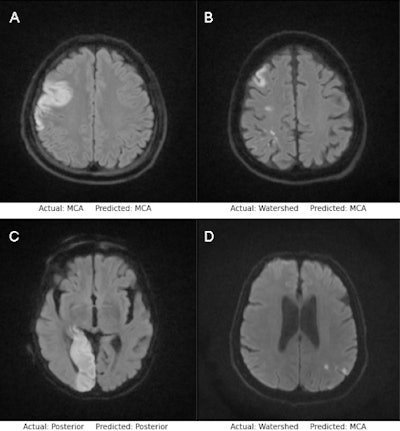

Examples of successful classification (A, C) and misclassification (B, D) by the MobileNetV2 model (top row) and EfficientNetB0 model (bottom row). Image courtesy of the European Journal of Radiology.Stroke is the second most common cause of death worldwide. Delays in both diagnosis and treatment in acute ischemic stroke seriously affect brain function and increase morbidity and mortality, the researchers stated. Managing patients with ischemic stroke requires the presence of human specialists, but specialists may not always be available in every health institution.

To that end, Cetinoglu and colleagues investigated the performance of two modified CNNs -- MobileNetV2 and EfficientNet-B0 -- for the detection of stroke as well as the areas where they occurred in the brain (vascular territories) on diffusion-weighted MRI.

Both CNN models performed well, the researchers found. The MobileNetV2 model achieved 96% accuracy in detecting the presence of stroke on DWI and the EfficientNet-B0 model achieved an accuracy of 93%.

In vascular territorial classification of stroke as middle cerebral artery, posterior circulation, or watershed infarction, the MobileNetV2 model achieved an accuracy of 93% and the EfficientNet-B0 CNN model achieved an accuracy of 87%.